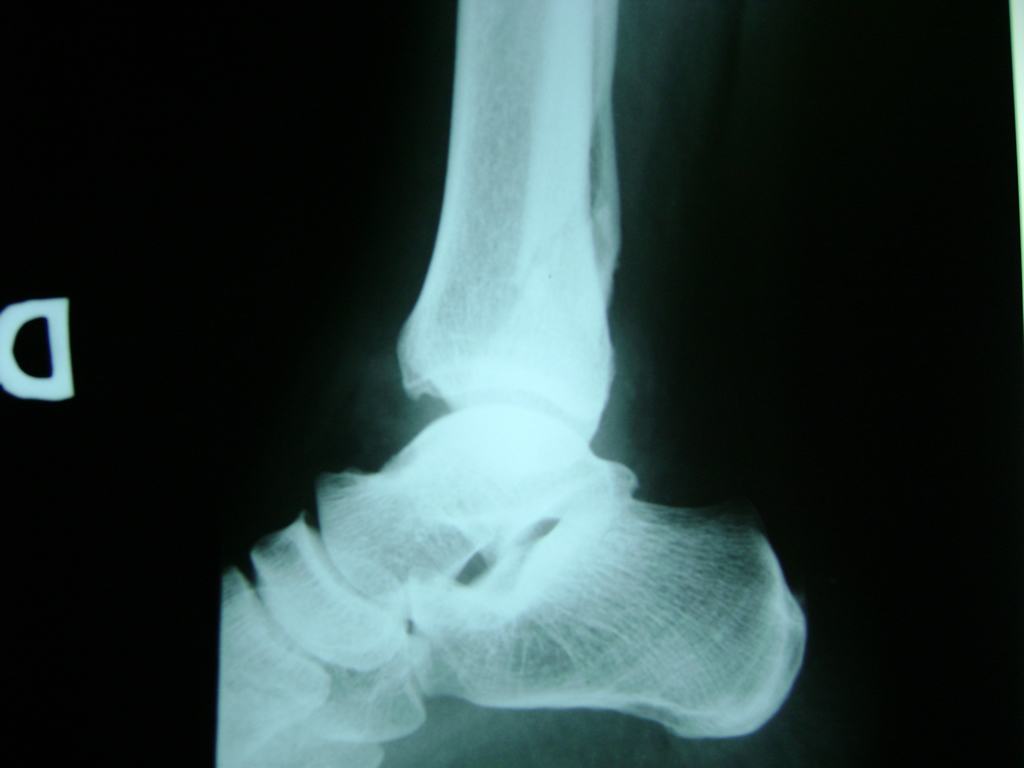

Una fractura de tobillo es la rotura de uno o más de los huesos del tobillo. Estas fracturas pueden ser:

- Parciales (el hueso está sólo parcialmente fisurado, no del todo).

- Completas (el hueso está perforado y está en 2 partes).

- Producirse en uno o ambos lados del tobillo.

Algunas fracturas de tobillo pueden requerir cirugía si:

- Los extremos de los huesos están desalineados entre sí (desplazados).

- La fractura se extiende hasta la articulación del tobillo (fractura intra-articular).

Cuando se necesita cirugía, es probable que esta implique el uso de clavijas de metal, tornillos o placas para sostener los huesos en su lugar mientras la fractura se consolida. Los elementos de soporte pueden ser temporales o permanentes.